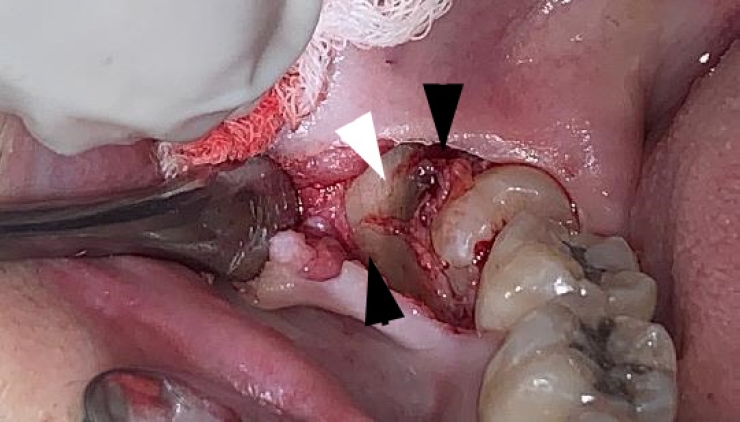

Intraoperatively, alternating bands of blue-gray and yellow discoloration of the alveolar bone was noted around both #38 and #48. (Fig. 2 and 3) No discoloration of adjacent teeth was observed. The overlying mucosa showed no discoloration or textural changes. During alveolar bone reduction, the bone density and quality appeared normal, and no other abnormal signs or symptoms were present.

Alternating bands of blue-gray and yellow discoloration of the alveolar bone observed during flap reflection for surgical extraction of the right mandibular impacted third molar.